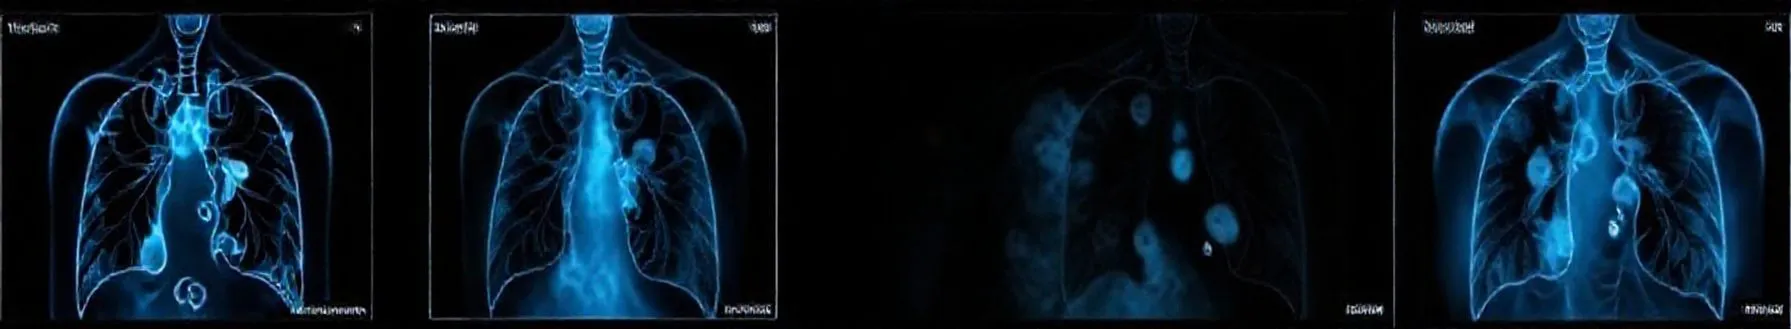

Pulmonary edema is a medical condition characterized by the accumulation of fluid in the lungs. It can be a life-threatening condition and requires prompt medical attention. It is often caused by an underlying medical condition or as a result of heart failure. When pulmonary edema occurs, the lungs...

- Pulmonary edema (PE) is a critical clinical condition characterized by fluid accumulation in the lungs due to fluid extravasation from pulmonary vasculature into the interstitium and alveoli. This flooding of alveoli impairs gas exchange, leading to hypoxia or hypercapnia. The pathophysiology involves an imbalance of Starling forces, damage to the alveolar-capillary barrier, lymphatic obstruction, or unknown mechanisms.